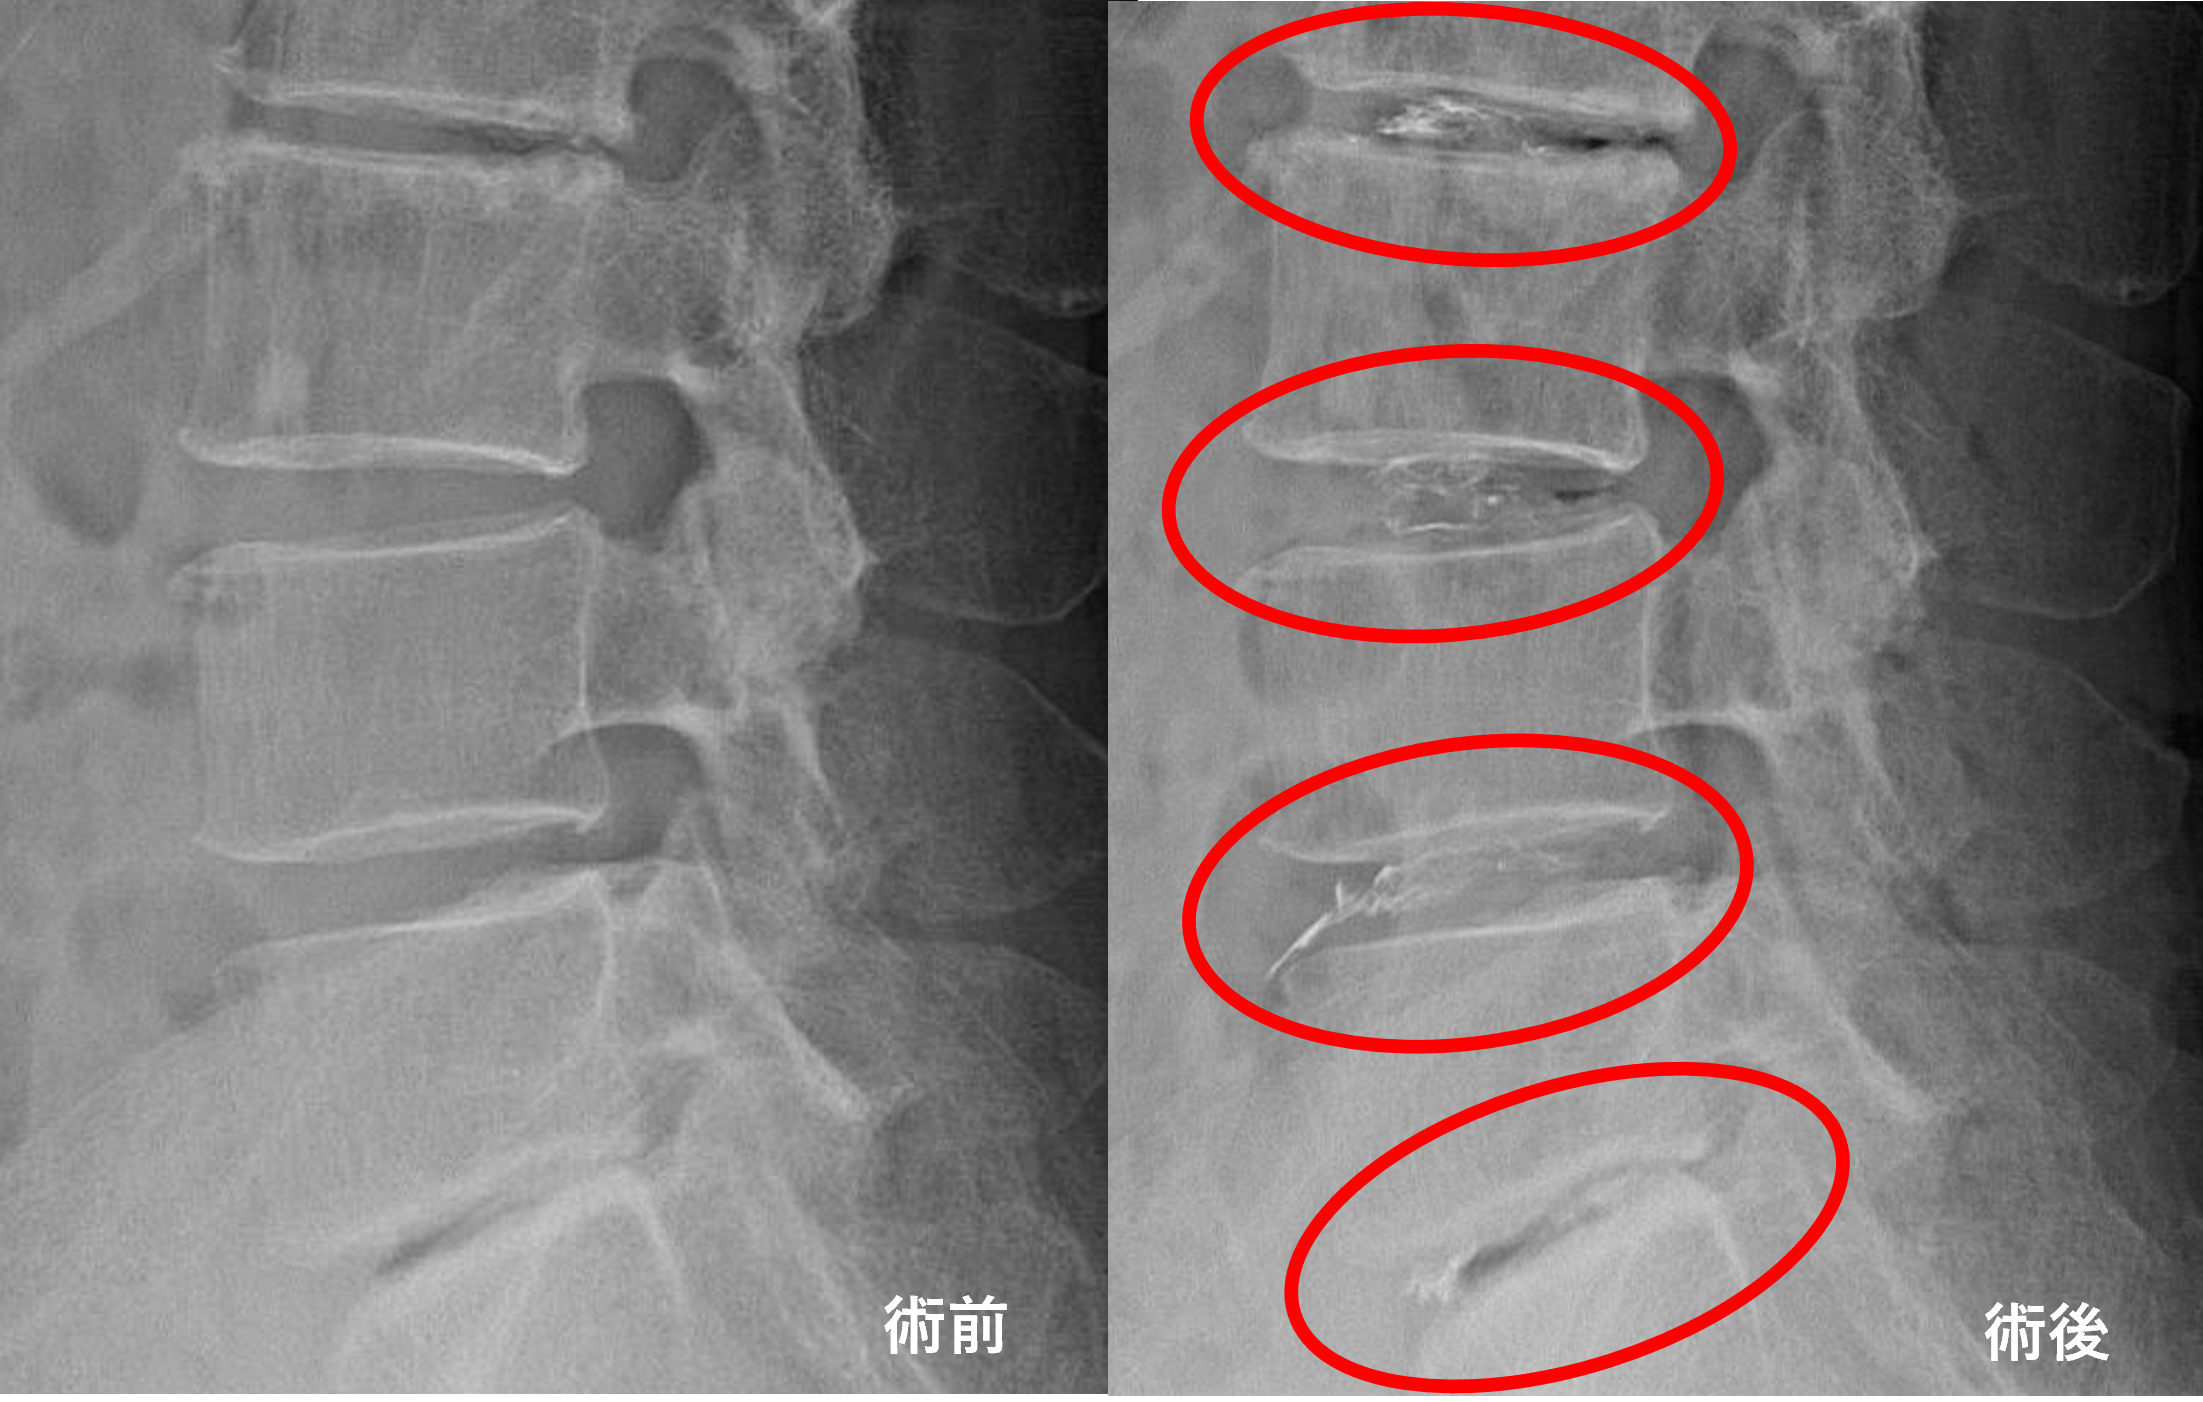

画像及び所見について

- L2/3、4/5、5/s – 椎間板変性、膨隆

- L3/4 – 椎間板変性、膨隆、脊柱管狭窄

以上のことが画像上認められました。

L2/3、3/4、4/5、5/sの椎間板所見による脊柱管の圧排が、症状の原因の可能性が高い。

患者様と相談の元、L2/3、3/4、4/5、5/sにセルゲル法を施行